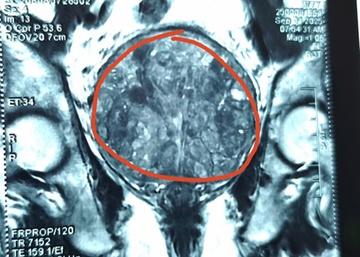

Một con sán bò có thể dài tới 10 m trong ruột. Nguy hiểm hơn, ăn thịt bò, lợn tái, nem chạo, tiết canh có thể đưa ấu trùng sán lợn vào cơ thể, chui lên não, gây co giật, mù lòa.